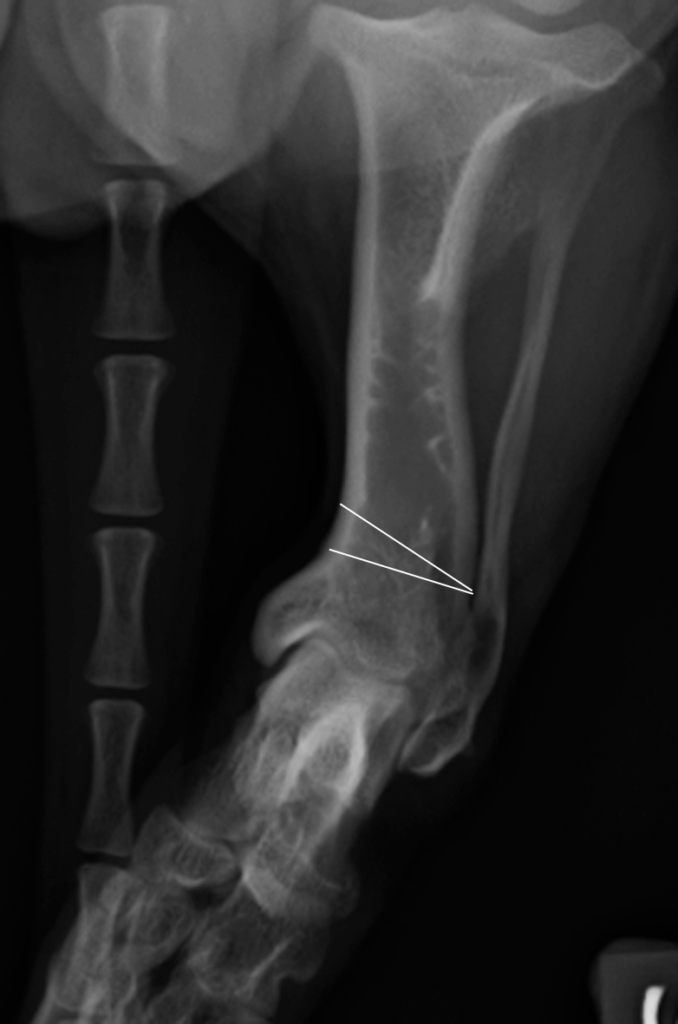

Diagnoosi voidaan varmistaa röntgenkuvauksella ja sairauden hoito on kirurginen. Sääriluun alapää katkaistaan ja luusta poistetaan kolmion muotoinen pala (kuva 2) niin, että jalka saadaan suoraan asentoon. Jalkaan asetetaan metallilevy (kuva 3A), joka poistetaan myöhemmin, kun leikkauskohta on täysin luutunut (kuva 3B). Fysioterapia leikkauksen jälkeen nopeuttaa paranemista. Ajoissa tehdyn leikkauksen ennuste on hyvä, ja suurin osa koirista elää leikkauksen jälkeen normaalin ontumattoman elämän.

Kuva 2: Leikkauksessa luusta poistetaan kolmion muotoinen pala niin, että jalka-akseli saadaan suoristettua.